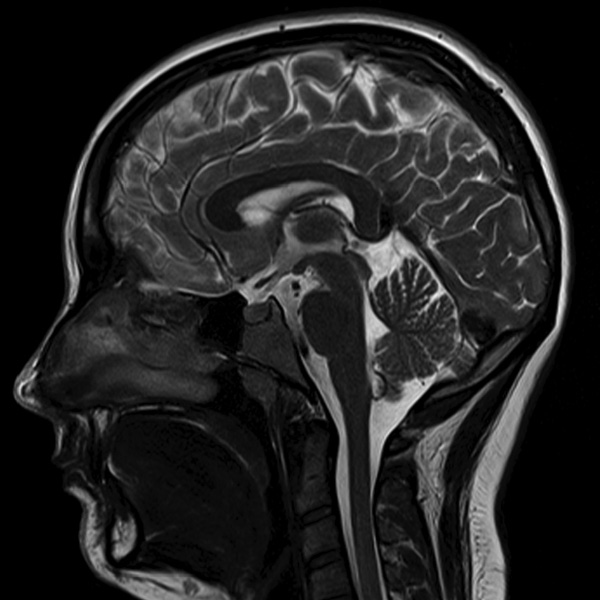

In the study, MRI scans were used to measure the oxygenation of blood flow in the brain in the study participants. The researchers developed a three- dimensional model of each individual’s brain by recording the number of connections between small blocks known as voxels (comparable to the pixels in an image) and the resulting change in these specific connections after given a single dose of escitalopram (Lexapro).

A whole-brain network analysis demonstrated that one dose of the SSRI actually decreased the level of intrinsic connectivity in the majority of regions of the brain. However, the researchers noted an increase in connectivity within two specific areas of the brain, the thalamus and cerebellum.